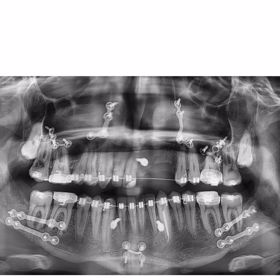

Dýdžej NobodyListen (27), vlastním jménem Jakub Strach, má po devíti letech důvod k radosti. Kvůli ošklivému zranění obličeje z minulosti musel podstoupit několik operací. Na Instagramu se pochlubil, že už může normálně kousat a znovu se naplno usmívat.

Zranění čelisti si NobodyListen způsobil před lety během jízdy na skateboardu. A jak redakce eXtra.cz před časem zjistila, bez zákroků by riskoval trvalé následky. „Kdyby ty zákroky, kdy mu předělávají celou čelist, nepodstoupil, tak by měl doživotní následky,“ svěřil se tehdy eXtra.cz zdroj, který byl s postupem léčby obeznámený.